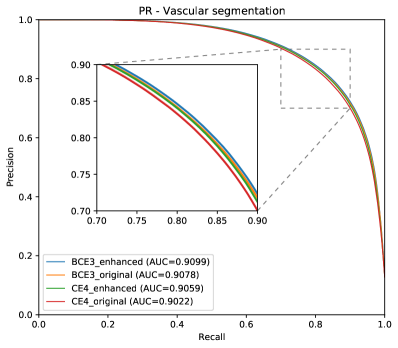

Complementing the segmentation results, Figure 10 depicts the ROC and PR curves of the different approaches for the A/V classification in the RITE-test set. These curves are built considering only the pixels labelled as “vessel” in the ground truth, being “artery” the positive class.

Regarding the artery/vein discrimination, although the MS alternatives achieve highly positive results (see Table 3), it cannot be affirmed that they perform better than the traditional alternatives. Considering the variability, the A/V classification results of both approaches are not significantly different. However, for the vessel/background discrimination, the situation is different. In this case, consistently with the higher AUC values for vessels segmentation, the MS approach achieves significantly better results () for both Accuracy and AUC-ROC. As can be seen in Table 3, when training with the original images, the sensitivity values of the MS approach are, on average, more than 2.5% higher than those of the traditional approach. Similarly, when training with the enhanced images, the improvement is about 1%. We focus on sensitivity, at a similar level of specificity, due to the positive class that is “vessel”, and the sensitivity measures the proportion of positives that were correctly identified. Specificity and accuracy, although they are also relevant, are much less sensitive in this scenario, since they take into account the background pixels, much more numerous and easier to classify.

The results depicted in Figure 12 are also in this line. Both methods, the traditional CE4 loss and the proposed MS with BCE3 loss, perform similarly when evaluated in simultaneous vascular segmentation and artery/vein classification. It is remarkable, however, that for a high vascular segmentation sensitivity the proposed approach achieves a slightly higher artery/vein classification accuracy.

In light of all these results together, it can be stated that the MS approach represents the more convenient alternative, since it is able to detect more vessels with similar A/V classification accuracy.